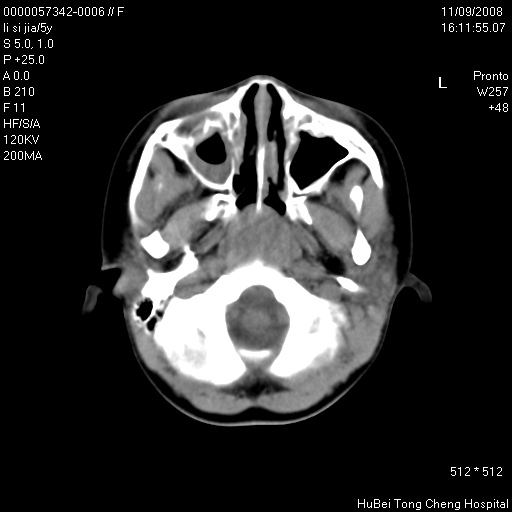

患儿 女,5岁。鼻塞、流涕2年余。

临床诊断:慢性副鼻窦炎?

副鼻窦ct轴位平扫(层厚、层距均为5mm),图像如下:

双侧上颌窦\\筛窦及蝶窦内均可见多量软组织密度影,结合病史支持考虑慢性全鼻窦炎

双侧上颌窦、筛窦及蝶窦内均可见粘膜增厚,结合病史支持考虑慢性全付鼻窦炎,腺样体肥大。